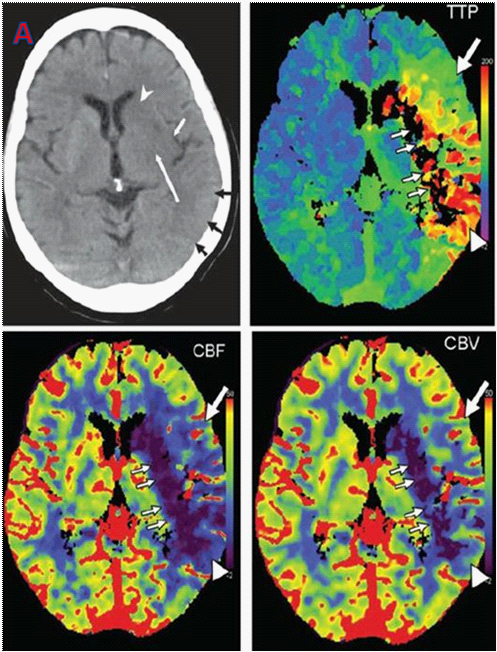

يُعتبر تضيّق الشرايين المغذيّة للدماغ من الأسباب الرئيسية للسكتات الدماغيّة، إلى جانب الصمُات الناتجة عن الرجفان الأذيني والاعتلال الأوعية الدقيقة. |

تؤدي الترسبات في الشرايين السباتية إلى تضيّق، وإذا ما انفصلت أجزاء من الترسبات والعصائد لتصل إلى الدماغ وتسد الأوعية الدماغية مُسببةً سكتة دماغية. وتُعزى 30 ألف حالة من أصل 200 ألف سكتة دماغيّة إقفارية إلى تضيّق الشريان السباتي حسب الدلائل الإرشاديّة الألمانيّة المصدرة في عام 2020. |

ويعاني الكثيرون من تضيق الشريان السباتي دون أعراض، وغالبًا ما يتم اكتشاف التضيق صدفة خلال الفحص الدوري عند طبيب الأسرة، طبيب الأعصاب أو طبيب القلب. وحتى الآن لم يوجد حل أمثل لمعضلة تضيق الشريان السباتي "الصامت"، أي الذي لم يُسبب أعراضًا بعد. واختلفت المدارس في توجيهاتها بين المدرسة المحافظة والتي تسعى لتقليل عوامل الخطر الوعائية كتنظيم ارتفاع الضغط الشرياني ومعالجة مرض السكري وتخفيض نسبة الدهون في الدم، بالإضافة إلى الابتعاد عن التدخين وتناول مثبطات الصفائح الدموية. |

أما المدرسة التداخلية فاختلفت بين التداخل الجراحي الوعائي (CEA)لإزالة العصائد الشريانية وبين التداخل الوعائي لوضع الداعمة في الشريان السباتي الداخلي (CAS). |

وحسب دراسة نُشرت في دورية NEJM قارنت دراستين شملتا 1245مريضًا من تضيق الشريان السباتي اللاعرضي في 155 مركزًا طبيًا في خمسة بلدن. وقارنت الدراسة الأولى، دراسة الدعامة (CAS) بين التداخل الوعائي والعلاج الدوائي، بينما قارنت دراسة التداخل الجراحي الوعائي بين الجراحة والعلاج الدوائي. |

كانت النقطة النهائية الأولية عبارة عن مزيج من السكتة الدماغية أو الوفاة، تم تقييمها في اليوم 44 بعد التوزيع العشوائي أو حدوث سكتة دماغية إقفارية من نفس جانب الشريان خلال أربعة سنوات بعد بدء الدراسة. |

في دراسة الدعامة وصل نحو 6٪من المشاركين في مجموعة العلاج الدوائي للنقطة الأولية، مقارنة ب 2,8٪ فقط من مجموعة التداخل الوعائي. أما في دراسة التداخل الجراحي فوصل 3,7٪ من مجموعة العلاج الجراحي للنقطة الأولية مقارنة ب5,3٪ من مجموعة العلاج الدوائي. |

وهكذا خلصت الدراسة إلى أن الجراحة لم تتفوق بشكل كبير على العلاج الدوائي مقارنة بالعلاج الوعائي. أما حسب دراسات المقارنة بين الطريقتين التداخليتين في حالة التضيق العرضي للشريان السباتي، فإن الجراحة والعلاج الوعائي بالدعامة متساويان، ويجب الاعتماد على الخبرات في المركز لتقرير استخدام إحدى الطريقتين. |